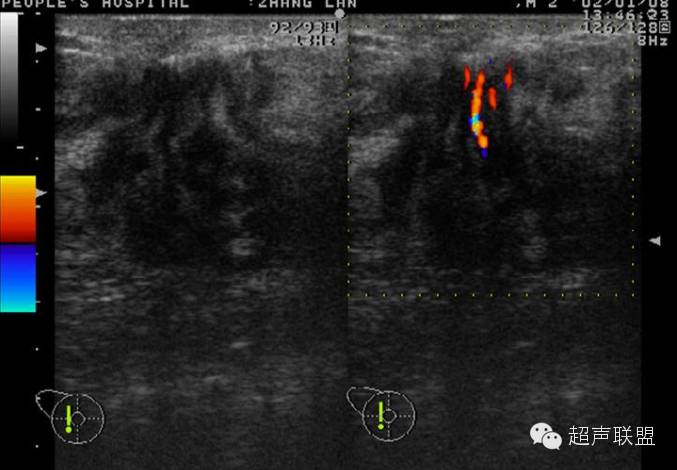

声像图表现:于右乳腺相当于六点钟,距约1.5cm处见一大小约1.0x0.6cm低回声肿物,边界尚清,形态不规,周边可检出动脉频谱样血流信号,RI为0.67,余腺体回声粗糙,未见占位性病变。右腋下另见数个淋巴结,较大的为1.4x0.8cm,边界清,周边呈低回声,中心部呈高回声。

超声印诊:1.右乳腺低回声肿物,性质待定

2.右腋下淋巴结肿大

病理结果:浆细胞性乳腺炎

签别诊断:主要是和乳腺Ca的签别,癌肿内还可以有“沙粒样”的微钙化灶,浆细胞性乳腺炎的病灶内血管多为低阻力型,RI一般小于0.70;乳腺癌的病灶内血管一般为高阻力型,RI多数大于0.70。(其机理是由于肿瘤血管在解剖结构上缺乏肌层,且没有一般血管从近端到远端逐渐变细的特点,导致局部受压,使血管阻力升高;而浆细胞性乳腺炎则无上述特点)。当图象上两者有交叉不好区分时,结合病史是最关键的,浆细胞性乳腺炎既往可有红、肿、热、痛的病史,急性期和亚急性期的结节有触痛,常有导管扩张,慢性期的结节可存在数年之久,抗生素治疗无效时,应想到本病的可能性;乳腺癌患者常无症状,仅触及包块,病史短,不伴导管扩张。